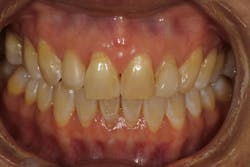

Gingival recession, more commonly described as the condition where the gum tissue surrounding the teeth pulls back, leading to root exposure, is a common periodontal concern (figure 1). Addressing this issue is not only crucial for maintaining oral health but also for achieving cosmetic satisfaction, particularly in individuals dealing with multiple teeth affected by recession (MAR).

PST, developed as a minimally invasive procedure, is designed to reposition gingival tissue to cover exposed roots.1,2 Unlike conventional methods, PST eliminates the need for grafting with tissue from the palate and invasive incisions, significantly reducing postoperative discomfort and scarring (figure 2).

Its application has garnered attention for restoring esthetics and improving oral health among patients with mild to moderate gingival recession in multiple sites.3,4 Recent studies have shown that the PST technique is comparable to the gold standard of soft-tissue grafting, which involves harvesting connective tissue from the palate or other areas of the patient’s mouth.1,2